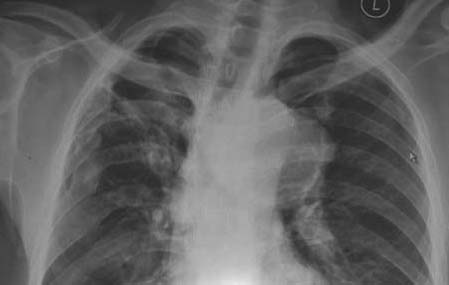

先传胸片一张,男,58岁,胸闷2年余。

sorry,胸片下些份因弄脏了切了,病变主要在上纵隔。

右侧陈旧肋骨骨折骨愈合。

右上肺陈旧病变。

右侧多发肋骨陈旧骨折,上纵膈占位,透光度较高,密度明显低于血管影,外缘“蛋壳样”钙化,皮样囊肿或囊性畸胎瘤?胸腺囊肿?上传ct吧!

气管受压变形,考虑纵隔占位。

右侧多发肋骨骨折已愈合,右上纵隔占位,侧位应在中纵隔,因为气管明显受压移位。结合外伤史,是否可考虑为假性动脉瘤,或是陈旧性纵隔血肿。降主动脉的边缘是清楚的,真性动脉瘤不太象,其形态也不对。年纪偏大,不考虑先天性疾病。